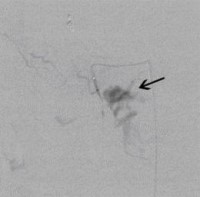

Postoperative abdominelle Blutungen bei chronischer Pankreatitis (Pfeile: Art. hepatica und Art. gastroduodenalis). (Bild 1 von 5) Vorwärts »

« Zurück Postoperative abdominelle Blutungen bei chronischer Pankreatitis vor Embolisation der Art. gastroduodenalis mittels Metallspiralen (Coils) (Bild 2 von 5) Vorwärts »

« Zurück Postoperative abdominelle Blutungen bei chronischer Pankreatitis nach Embolisation der Art. gastroduodenalis mittels Metallspiralen (Coils) (Bild 3 von 5) Vorwärts »